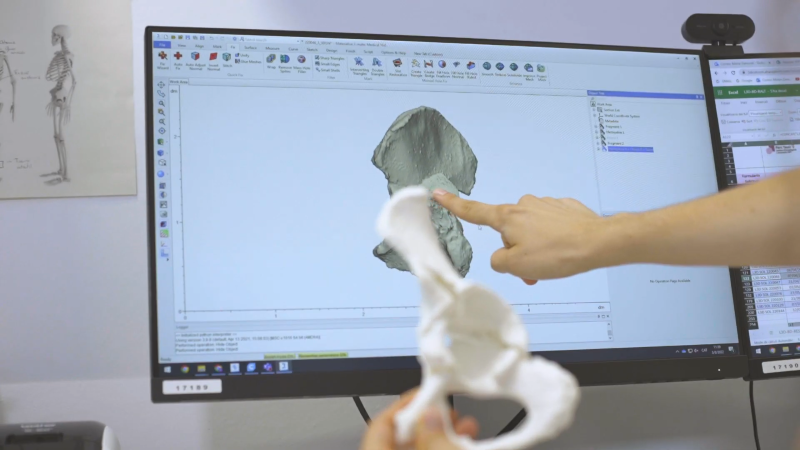

Aquesta solució ha consistit en un conjunt d’eines i programes informàtics per al disseny, planificació i impressió 3D no aplicades fins ara a l’assistència sanitària, que funcionen de manera coordinada per agilitzar i millorar la qualitat dels processos quirúrgics. En concret, la solució incorpora: impressores 3D que amplien la capacitat productiva de l’I3PT i redueixen els temps en la fase de disseny; eines d’escaneig 3D per al mesurament de precisió preoperatòria de forma no invasiva que permeten l’avaluació de tot el cos per a optimitzar la biomecànica personalitzada, substituint així en algunes ocasions el TAC; i programari per a monitorar i realitzar un seguiment de principi a fi dels processos de fabricació i quirúrgics, garantint la qualitat necessària per a produir una pròtesi biomecànica personalitzada.

Planificació quirúrgica virtual per artroplàstia de maluc (foto superior) i espatlla (foto inferior)